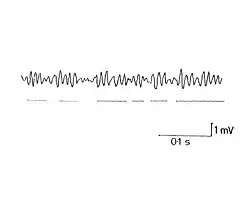

Ocular microtremors (OMTs) are small, quick, and synchronized oscillations of the eyes occurring at frequencies in a range of 40 to 100 Hz, although they typically occur at around 90 Hz in the average healthy individual. They are characterized by their high frequency and minuscule amplitude of just a few arcseconds. Although the function of ocular microtremors is debatable and not fully known, they seem to play a role in processing of high spatial frequencies, which allows for perception of fine detail.[26][30][31] Studies show that ocular microtremors have some promise as a tool for determining the level of consciousness in an individual,[32] as well as the progression of some degenerative diseases including Parkinson's disease[33] and multiple sclerosis.[34]

Although originally thought to stem from spontaneous firing of motor units, the origin of ocular microtremors is now believed to be in the oculomotor nuclei in the reticular formation of the brainstem.[35] This new insight opened the possibility of using ocular tremors as a gauge for neuronal activity in that region of the central nervous system. More research must be done, but recent studies strongly suggest that decreased activity in the brainstem correlates with decreased frequency of OMTs.[36]

Several methods of recording have been developed to observe these minuscule events, the most successful being the piezoelectric strain gauge method, which translates eye movement through a latex probe in contact with the eye leading to piezoelectric strain gauge. This method is used in research settings; more practical adaptations of this technology have been developed for use in clinical settings to monitor the depth of anesthesia.[37] Despite the availability of these methods, tremor remains more difficult to measure than other fixational eye movements, and studies addressing medical applications of tremor movements are rare as a result.[20] Some studies have, nevertheless, pointed to the possibility that tremor movements may be useful in assessing the progression of degenerative diseases including Parkinson's disease[33] and multiple sclerosis.[34]